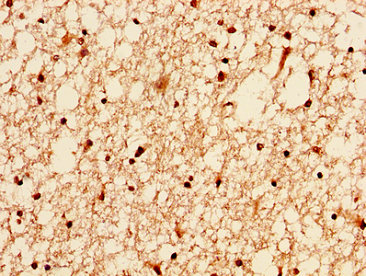

IHC image of CSB-PA010100OA04nacHU diluted at 1:50 and staining in paraffin-embedded human brain tissue performed on a Leica BondTM system. After dewaxing and hydration, antigen retrieval was mediated by high pressure in a citrate buffer (pH 6.0). Section was blocked with 10% normal goat serum 30min at RT. Then primary antibody (1% BSA) was incubated at 4°C overnight. The primary is detected by a biotinylated secondary antibody and visualized using an HRP conjugated SP system.